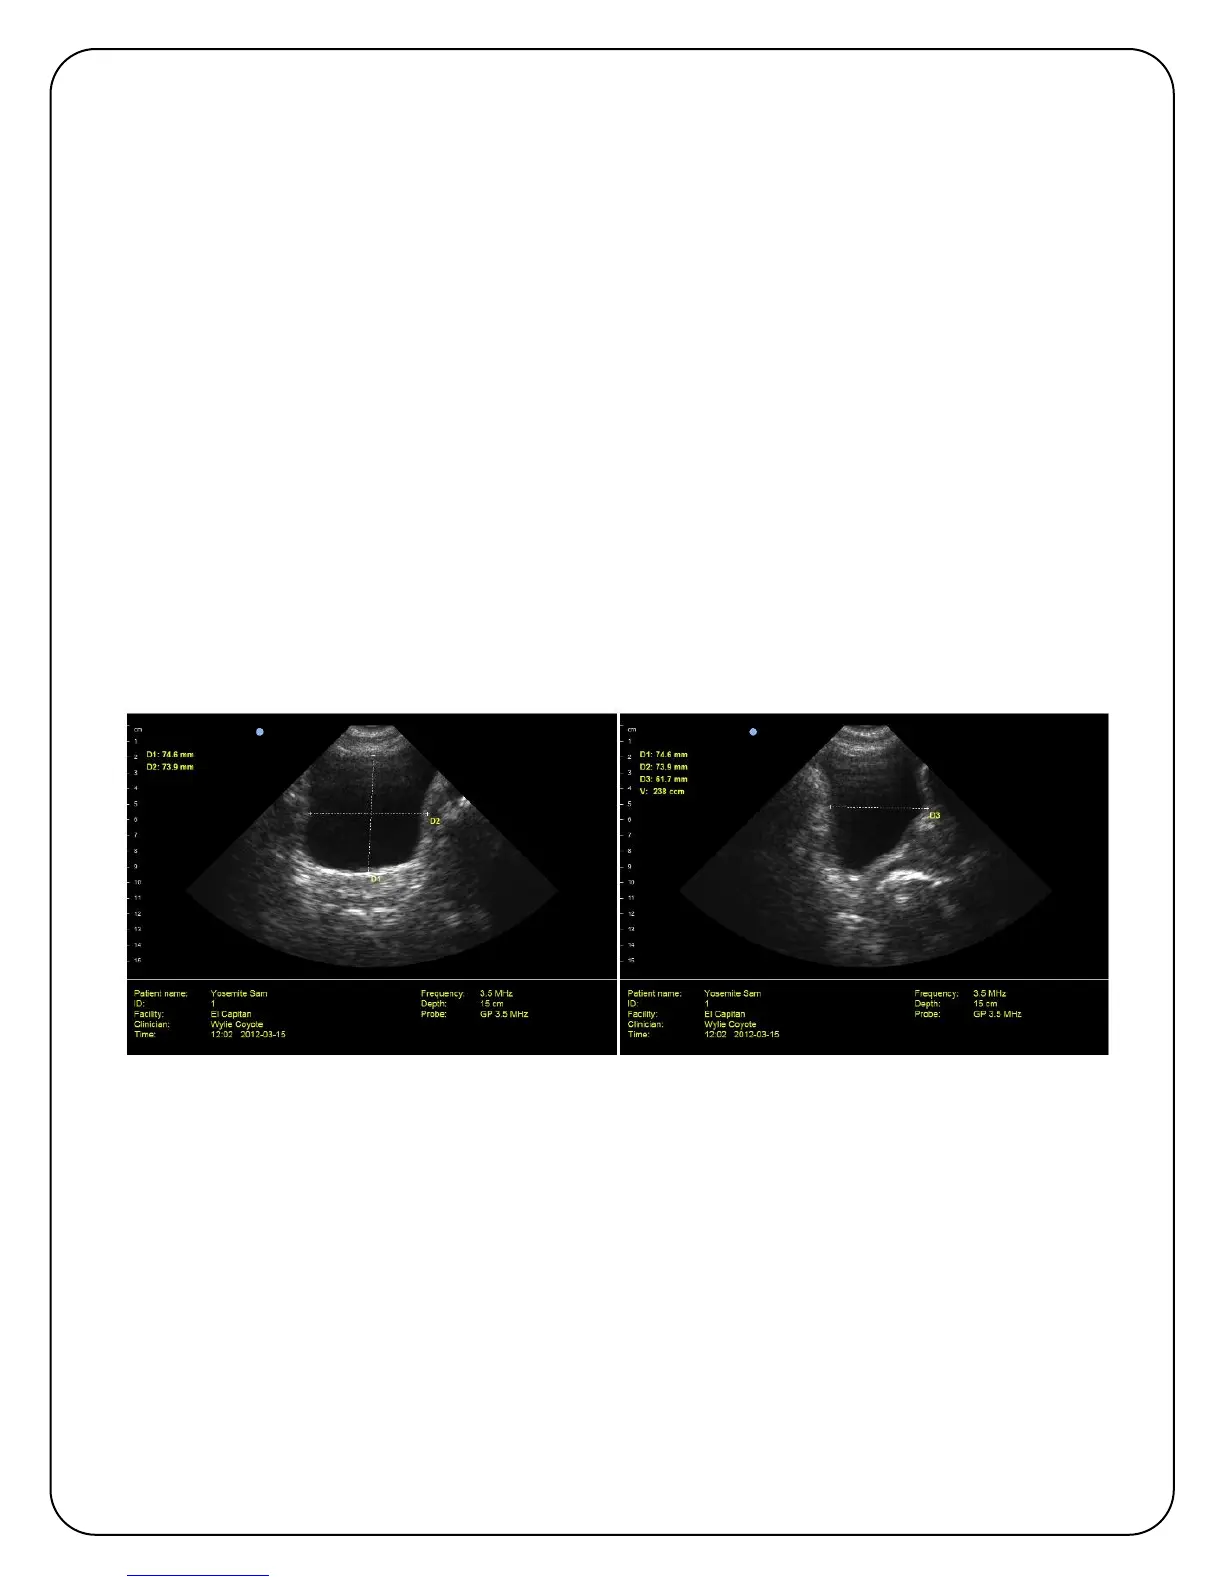

6. After freezing the image, measure the height of the displayed bladder by placing your finger

on one edge of the bladder and swiping to the opposite side. Similarly measure the width.

7. Follow the onscreen prompts, displayed in yellow beneath the patient exam box, to take the

mid-sagittal scan. By rotating the probe 90 degrees you will be viewing the thickness of the

bladder. Start the scan and then freeze when you have the optimal bladder image.

9. Measure the thickness of the bladder by placing your finger on the edge of the bladder and

swiping to the opposite side. The mid-sagittal bladder image is often displayed at a slight

angle, either up or down. Therefore to make the most accurate measurement, always

measure the thickness at the appropriate angle.

10. ViewBladder 10 will calculate and display the bladder volume. If you find you did not optimally

place your finger, double tap to remove the volume calculation and the distance

measurement. Repeat the distance measurement.